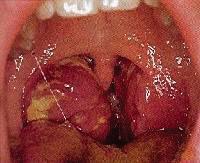

КОГАТО ПРИЧИНИТЕЛИТЕ СА ОТ ГРУПА А

Streptococcus β-хемолитични или Epstein-Barr

вирус могат да предизвикат клинична изява на петехии по небцето. Обикновено се наблюдава при деца на възраст от 5-15 години. Те дишат с отворена уста и имат променен

глас (т.е. по-дебел или по-дълбок глас) в резултат на обструкцията на тонзилите. Увеличени-

те лимфни възли по шията могат да дадат скованост на движението на шията. Промяната на

тургура на кожата и лигавиците са признаци на дехидратация. В дифиренциално-диагностичен план трябва да се мисли за инфекциозна мононуклеоза, особено, когато има лифаденопатия на шийните, аксиларните, и/или ингвинални възли; спленомегалия, тежка летаргия, общо неразположение и субфебрилна температура с придружаващ остър тонзилит. Тук важна роля изграят параклиничните изследвания: моноцити, реакция Паул Бонел и др. Когато има инвазия с вируса на херпес симплекс (HSV) клинически тонзилите се представят със силно хиперемирани, оточни сливици, които могат да имат и афтозни язви върху тях (Фиг.3). Паралелно с това може да се засегнат и венците с развитие на тежък стоматит, херпес лабиалис и лезии на хипофаринкса и епиглотиса. Скарлатинозният тонзилит се предизвиква от Str. pyogenes гр. A и протича с огнени-зачервявания на фарингеалната лигавица (енантем), малиненочервен език с екзантем – финопетнисто, дифузно зачервяване по кожата на главата, шията, туловището и периорална бледност. Пневмококовият тонзилит има хиперемия и оток на тонзилите, сиво-бели, лесно отстраними налепи, конфлуиращи по меко небце и увула. Улцеро-мембранозната ангина се предизвиква от фузиформени пръчици (Fusibacterium fusiforme) и спирали (Borrelia vincenti). Тя обикновено е едностранна с нали-

Фиг. 1

Клиничен прегледмезофарингоскопия

Фиг. 2

Остър бактериален тонзилит

Фиг. 3

Разлика между вирусни и бактериални ангини

Фиг. 4

Перитонзиларен абсцес